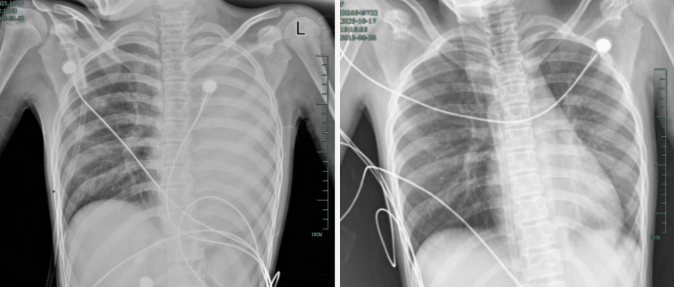

治疗前后影像对比,左肺从“白肺”到正常状态。

据介绍,笑笑一开始只是轻微咳嗽,发热到38℃,检查提示肺炎肺不张,转诊到浙大四院儿科时,病情已经急剧恶化,出现呼吸急促、胸闷胸痛,体温38.5℃,只能靠5L/min的面罩吸氧维持血氧,胸片显示左肺已完全呈 “白肺” 改变,肺部炎症进展迅猛。